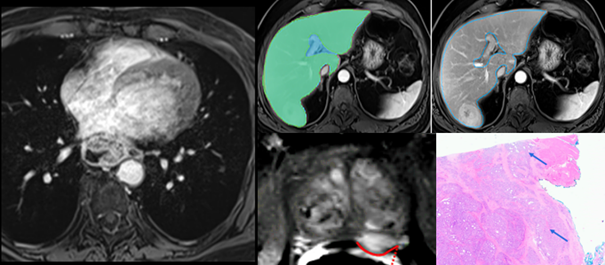

1. Hepatic and Functional Imaging: The management of patients with chronic liver diseases such as cirrhosis, including those with hepatocellular carcinoma (HCC), lies at the heart of our hepatic imaging research. Additionally, we develop quantitative Ultrasound and MRI methods (DWI, T1/T2 mapping, fingerprinting) to assess liver function in conditions as cirrhosis, fibrosis, steatosis and HCC. Collaborations with the Microstructure Mapping Lab of UNIL, EPFL and CIBM but also with our colleagues from other specialties such as hepatologists, oncologists and surgeon help tailor these tools to clinical needs.

3. AI and Radiomics in Oncology Imaging: We collaborate on radiomic signature identification and AI-based tools for liver, pancreas, and esophageal cancers. Deep learning models enhance HCC detection and clinical decision support. Collaborations with the Translational Machine Learning Lab, HES-SO Valais are key for success.